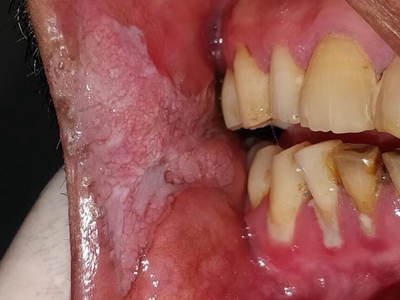

口腔

白斑

颊癌一边颊黏膜有白斑图

颊癌患者口腔一侧颊黏膜出现形状不规则的白斑,边界较为清晰,周围有炎性红晕,患者常以为是普通的口腔溃疡而没有加以重视,从而导致其侵犯周围及深层组织。